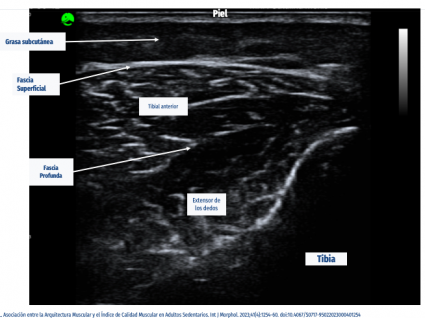

Constanza Rivas señala que, en base a dicha evidencia, los tejidos del sistema musculoesquelético en personas que poseen trastornos musculoesqueléticos no han sido estudiados. En ese sentido, decidió apuntar al tejido muscular para su investigación, siendo uno de los tejidos que posee mayores funciones de movimiento, además de ser un predictor de salud y de mortalidad, por lo que observó la calidad muscular y evaluar de manera funcional y morfológica los tejidos de una muestra de 101 profesores.